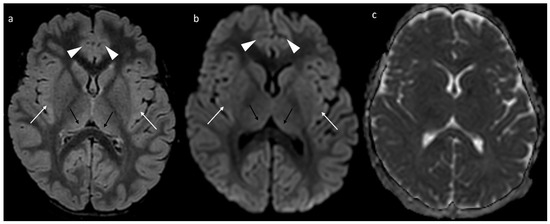

Non-Convulsive Status Epilepticus and Mild Neurodevelopmental Phenotype in a Female with a Novel p.Thr657Ala Variant in the GRIA3 Gene

Background: The GRIA3 gene encodes the GluA3 subunit of AMPA-type glutamate receptors, which are crucial for excitatory neurotransmission in the central nervous system. Pathogenic GRIA3 variants cause X-linked neurodevelopmental disorders of varying severity, including developmental delay, behavioral abnormalities, and epilepsy. Case Summary: Here, [...] Read more.

Background: The GRIA3 gene encodes the GluA3 subunit of AMPA-type glutamate receptors, which are crucial for excitatory neurotransmission in the central nervous system. Pathogenic GRIA3 variants cause X-linked neurodevelopmental disorders of varying severity, including developmental delay, behavioral abnormalities, and epilepsy. Case Summary: Here, we present the case of a seven-year-old female patient presenting with developmental delay, spastic gait, and non-convulsive status epilepticus (NCSE), who was found to carry a novel de novo GRIA3 missense variant (c.1969A > G; p.Thr657Ala). The EEG revealed high-amplitude diffuse rhythmic theta/delta activity consistent with NCSE. A brain MRI showed transient cortical and thalamic T2-FLAIR hyperintensities, likely postictal. Metabolic investigations were unremarkable. Following intensive treatment with levetiracetam and midazolam, the patient gradually recovered to her baseline neurological status. Genetic Finding: Whole-exome sequencing (WES) identified a novel de novo variant in GRIA3, c.1969A > G; p.Thr657Ala, involving the replacement of threonine with alanine at position 657 within the coding region. Significance: This case expands the clinical and molecular spectrum of GRIA3-related disorders, demonstrating that females with de novo variants may experience severe epilepsy. This is the first reported case of NCSE in a female patient with a GRIA3 variant. Full article